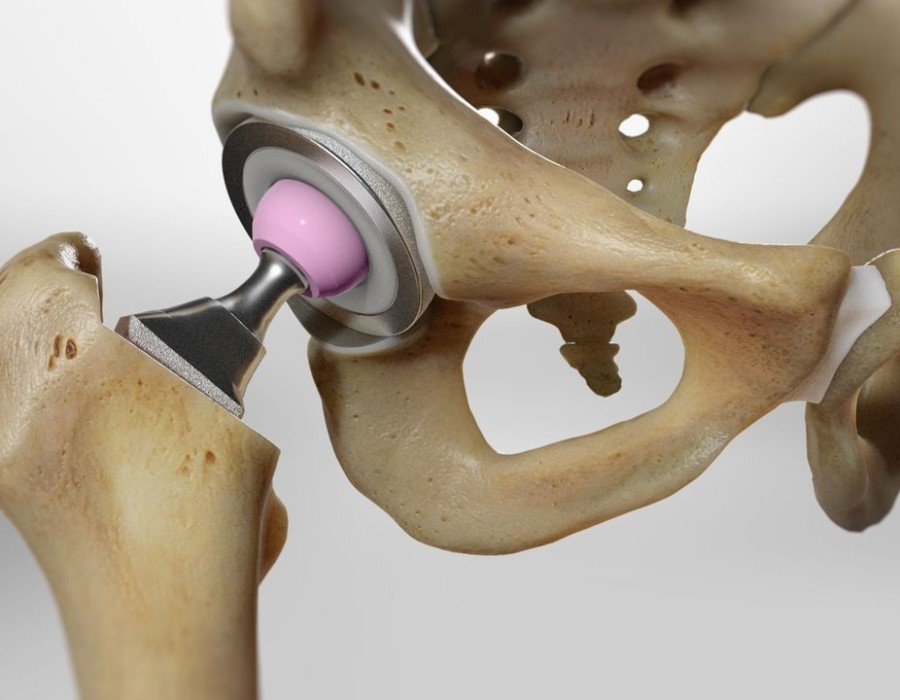

Chirurgiese opsies en inplantingsmateriaal: Daar is verskillende benaderings tot heupvervangingschirurgie, insluitend tradisionele of minimaal indringende tegnieke. Daarbenewens kan inplantingsmateriaal soos keramiek, metaal of plastiek verskil, en jou chirurg sal help om te bepaal watter die beste vir jou gesondheid en lewenstyl sal werk.